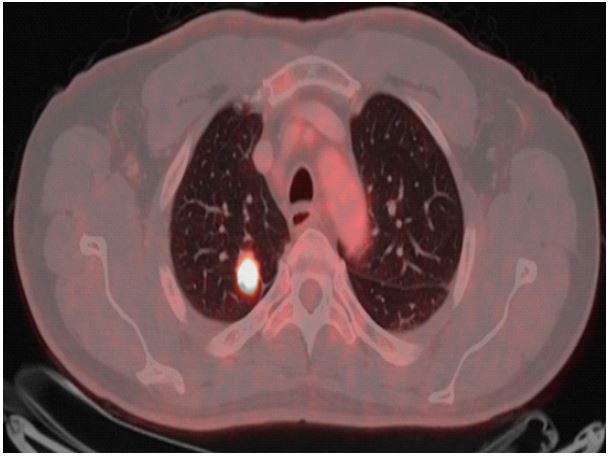

The MA test results of the case report subject indicated a response profile to tumor-associated peptides corresponding wells with a subject with LC malignancy. As a result, the case report subject was clearly suspected to have LC. He was referred for further clinical investigation at the Rambam Medical Center Haifa, Israel. As the Liquid ImmunoBiopsy™ MA test results showed a high-risk metabolic profile for malignancy, the patient was referred to low-dose computed tomography (LDCT) that revealed a 20 x 19 x 16 mm right upper lobe mass with no hilar or mediastinal lymphadenopathies (Figure 2). He underwent a PET scan examination which showed increased 18F-fluorodeoxyglucose (FDG) uptake only in the right upper lobe mass, thus raising a high suspicion for early lung cancer (Figure 3). After a preoperative evaluation that revealed normal lung function test, the patient underwent a uniportal thoracoscopic right upper lobectomy (VATS) with mediastinal lymph node dissection. Patient had uneventful recovery from the surgery and was discharged on postoperative day 2. Pathology confirmed a diagnosis of stage IA (T1b N0 m0) well differentiated adenocarcinoma, 1.5 cm in diameter, with 9 mediastinal and hilar lymph nodes without evidence of metastasis.

Figure 3: PET-CT image The 18F-fluourodeoxyglucose positron emission computed tomography showing increased 18F-fluorodeoxyglucose (FDG) uptake in the right upper lobe mass.

Recently, we recruited to the healthy control group of a clinical trial study a subject who does not have a smoking history and does not belong to any high-risk group for lung cancer. The MA-LC ImmunoBiopsy™ test’s result of his blood sample indicated a response profile to tumor associated peptides of a subject with malignancy, and this blood donor was clearly suspected to have LC. The person was referred for further clinical investigation which included LDCT and PET-CT screening. LDCT showed a suspected lesion (Figure 2). The PET-CT image showed that this lesion is highly suspected to be malignant (Figure 3). Following these findings, he underwent thoracoscopic right upper lobectomy. The malignant tumor was removed and identified as NSCLC adenocarcinoma stage IA. The early detection of lung cancer by the MA-LC ImmunoBiopsy™ test and the subsequent surgery treatment to remove the malignant tumor is expected to lead to a high probability of a full recovery from the LC. We reported4 that the MA-LC ImmunoBiopsy™ test provides results within five hours of receiving the blood sample for MA-LC. The analytical sensitivity of the test is high, with a lower limit of quantification (LLOQ) of 0.000119 (d/minute) in change of acidity over time. It specifically quantifies glycolysis, which is a biomarker for the activation level of immune cells that are re-exposed in-vitro to lung TAA stimulants. Currently, liquid biopsy is mainly utilized as an auxiliary tool in lung cancer diagnosis, when a LDCT detects an abnormality. We believe that the non-invasive MA-LC ImmunoBiopsy™ test, with its low material costs, fast results, and a patient-friendly blood test character, has a potential to be an integral part of lung cancer mass screening programs for high risk populations first and foremost, but as shown in this case, also for a broader population without high risk.